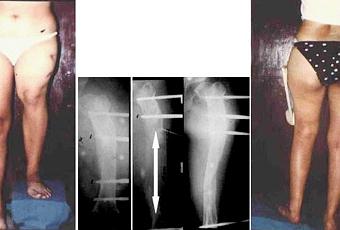

Fig. 3. Varón de 28 años que tuvo una grave fractura abierta por arma de fuego con amplia daño de tejidos blandos y severa infección al borde de la amputación. Se le retiraron los tejidos muertos e infectados haciéndole un acortamiento de 12 centímetros. Luego de mejorar los tejidos se inició su alargamiento para recuperar la longitud normal. Curó sin infección ni acortamientos.La aplicación requiere de algún entrenamiento y generalmente son las nuevas generaciones de cirujanos traumatólogos -con alguna experiencia- quienes más los usan. No obstante, en el campo de los fijadores externos existe un gran problema: la cantidad de modelos desarrollados en el mundo, por lo menos 300, desde los más simples hasta los más sofisticados y costosos (cuatro, ocho, diez mil dólares cada uno). Por tanto se hace complicada la elección del tratamiento con estos aparatos, por un lado, siendo tantos los modelos, cuál sería el elegible, y por el otro, sus costos. Además cada modelo requiere de su propio instrumental y propios pasos de técnica operatoria, algo mas, no todos los “fijadores externos” tienen la misma versatilidad ni tampoco ofrecen el rendimiento esperado. Hay grandes diferencias. Unos son simples “dispositivos inmovilizadores” y otros tienen mecanismos para ayudar al cirujano en las maniobras de acomodación (reducción), de tracción o de compresión. Igualmente, se diferencian en su aspecto externo, unos son impresionantes y otros son de aspecto tolerable para el infortunado paciente.

Fig. 4. Secuela de fractura abierta consolidada en mala posición y en acortamiento. Obsérvese la corrección por simple osteotomía y su subsiguiente alargamiento.¿A que se debe la aparición de tantos (más de 300) Fijadores Externos?Consideramos fundamentalmente, a la falta de disponibilidad de estos aparatos en ambientes hospitalarios traumatológicos modestos, donde el médico intuye que son aparatos útiles, pero costosos y sofisticados. Esto hace que, al no disponerlos, se tenga la imaginación de crearlos, o, mas fácil, de copiarlos o hacerle modificaciones a los ya conocidos, pero que estén disponibles y sirvan para resolver el problema.Consideramos también a la natural tendencia de la “creatividad mecanicista” que existe espontáneamente en el hombre, con la absoluta confianza de que su creación (su aparato), puede ser de última generación, que supera a lo actual, y por supuesto, con expectativas de ganancias económicas.